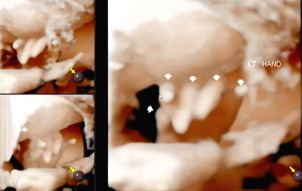

입체 초음파 또한 복부초음파처럼 침대에 누워 태아의 상태를 확인하는데 정밀검사처럼 태아의 손, 발뿐 아니라 얼굴 생김새까지 확인이 가능하다.

바른 자세로 누워 초음파를 시작했다. 손가락, 발가락뿐 아니라 양측 귀까지 입체 초음파를 통해 확인하고 태아의 얼굴 생김새를 확인했다. 일반 초음파로 확인할 때와 다르게 입체적으로 보이는 태아의 모습에 신기했다.

다른 부분을 확인하고 태아의 얼굴을 보기 위해 초음파를 시작하는데 아기가 자궁벽을 향해 얼굴을 붙이고 있어서 초음파에서 얼굴을 보기 힘들었다. 입체 초음파로 생김새를 정확히 보기 위해서는 태아가 양수가 많이 있는 방향으로 얼굴을 가리지 않아야 한다. 햇님이는 벽에 얼굴을 붙인 것뿐 아니라 손으로 얼굴을 가려서 더욱 보기가 힘들었다. 사실 입체 초음파를 보기 전 일반 초음파를 확인할 때 얼굴을 보기 힘들었어서 이번에도 어려울 거라고 예상은 했었다. 그래서 초음파를 확인하는 선생님이 나의 배를 열심히 흔들었다. 태아가 양수의 흔들림에 자세를 바꾸기를 바라며 나의 배를 흔들고 눌렀는데 초음파에서 얼굴 정면을 볼 수 없었다.